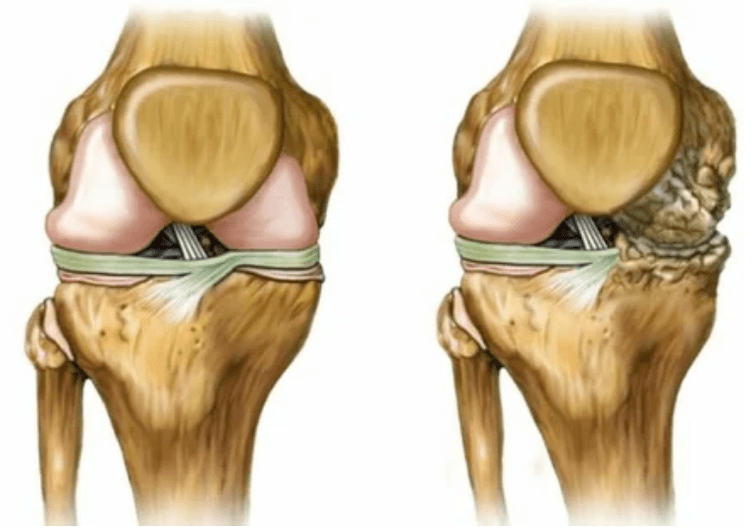

- Stage 2. The necessary cartridges are destroyed due to supply failure, bone growths occur on the surface of cartilage.The pain gets a clearer character, strengthens after a long rest, eliminated by small physical labor.The pain is accompanied by inflammation.The muscles are lying that causing weakness or average impaired motor functions.

- 3 degrees.There are often pains, it is difficult to move according to the playful change.Lesions are wide, noticeable for the naked look.The deformation of the joint site occurs, the affected region is inflated and red.The limitation reading is concerned, which leads to the complexity of the action.Pathological changes shortened the ligaments.Sublishes and contracts appear.Neighboring muscles are shortened or stretched, the contract function weakens.